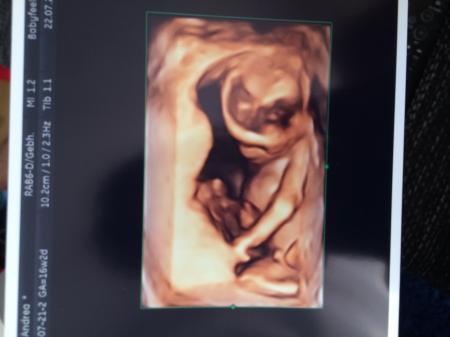

Hallo meine lieben Mit-kuglerin, Ich war letzte Woche bei einem Ultraschallstudio und haben versucht das Geschlecht zu erahnen. War da ich 16+2. Sie war sich da ziemlich sicher, dass es ein Junge ist. Aber wenn ich mir die Fotos so in Google anschaue finde ich kein vergleichbares, denn mir fehlen auf den Fotos die Hoden bzw. ist der Penis kleiner als auf den Vergleichsfotos. Wir haben zwar schon einen jungen, aber das Geschlecht konnte man bei ihm deutlich beim 2. Screening sehen. Ich weiss, dass kein Weg dran vorbeiführt noch drei Wochen auf das 2. große Screening zu warten, aber würde trotzdem gerne eure Meinungen wissen

Bild zu Wirklich ein Junge?! - Schwanger - wer noch? Rund um die Schwangerschaft

Hallo meine jungs sahen beide auch so aus in der 15 und 16 ssw. lg nita

wie süß! Was man heute auf diesen Bildern so sehen kann. Meine Schwangerschaften liegen schon ein Weilchen zurück und bei uns wurden immer nur die normalen 2 D Bilder gemacht. Klasse, was heute geht. Aber zur Frage: Ich würde da auch sagen, dass das ein Junge ist.

Ich würde auch sagen,Bub ;) Vor allem auf dem 2D Bild würde man beim Mädchen die typischen Striche sehen ("Brötchen").